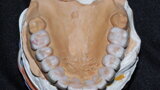

Figure 30 Madibular occlusal view